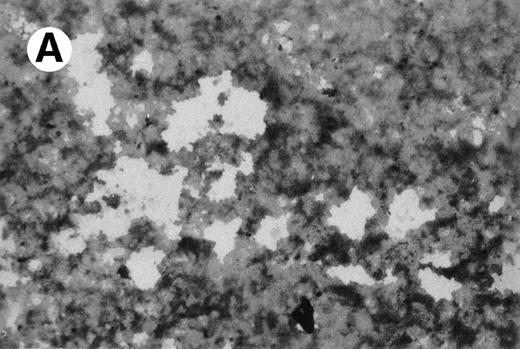

UG3 cells preincubated with 100 ng/mL M-CSF for 2 weeks formed multinucleated giant cells displaying TRAP activity when cultured for an additional 2 weeks in the presence of both 100 ng/mL M-CSF and 100 U/mL IL-4 (Fig10). UG3 cells did not form multinucleated giant cells when cultured with M-CSF alone for the whole observation period of 4 weeks (not shown). UG3 cells cultured in osteologic slide flasks in IMDM with 5% FCS supplemented with M-CSF and IL-4 resorbed larger amounts of hydroxyapatite (Fig 11A) than those cultured with IL-3 and IL-4 (Fig 11B).

Resorption of hydroxyapatite by osteoclast-like giant cells exposed to M-CSF and IL-4. Hydroxyapatite was stained black by Von Kossa staining. UG3 cells that had been cultured in the presence of M-CSF (100 ng/mL) and IL-4 (100 U/mL) had pericellular clear areas (A) resulting from hydroxyapatite resorption, whereas those that had been cultured in the presence of IL-3 (5 ng/mL) and IL-4 (100 U/mL) did not (B). Original magnification, 30-fold. Histochemical analysis was performed with cells obtained from three independent cultures.